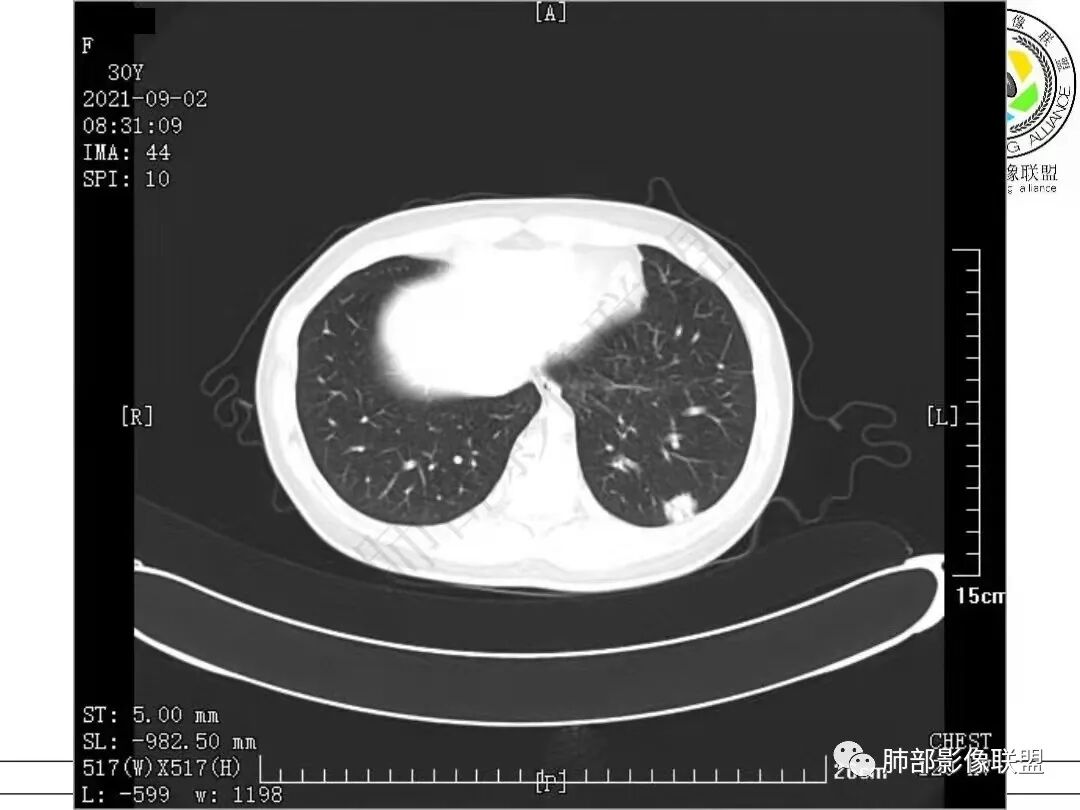

1.病例一:68岁男性,体检发现肺结节,肿瘤标志物CA199、CA50、CEA升高,其中CEA升高显著,超过正常范围的5倍以上。右肺下叶胸膜下结节影,整体较膨隆,部分层面可见锯齿状边缘,边界清晰,周围可见细毛细影,可见血管集束征、胸膜牵拉。密度不均,可见磨玻璃密度区及空泡征,胸膜下脂肪间隙显示不清。增强后显示轻、中度强化。

综合分析:两份病例都是位于胸膜下的孤立结节,同样具有锯齿状边缘,有细毛刺、空泡。病例一老年男性+CEA显著升高,常规恶性病变肯定是要考虑;至于病例二青年女性,肿瘤标志物阴性,在未见非常典型恶性征象情况下,临床通常会优先选择炎性病灶进行处置,病灶持续存在,复查无变化或出现进展,则应想到新生物可能,而选择穿刺或其他进一步检查。